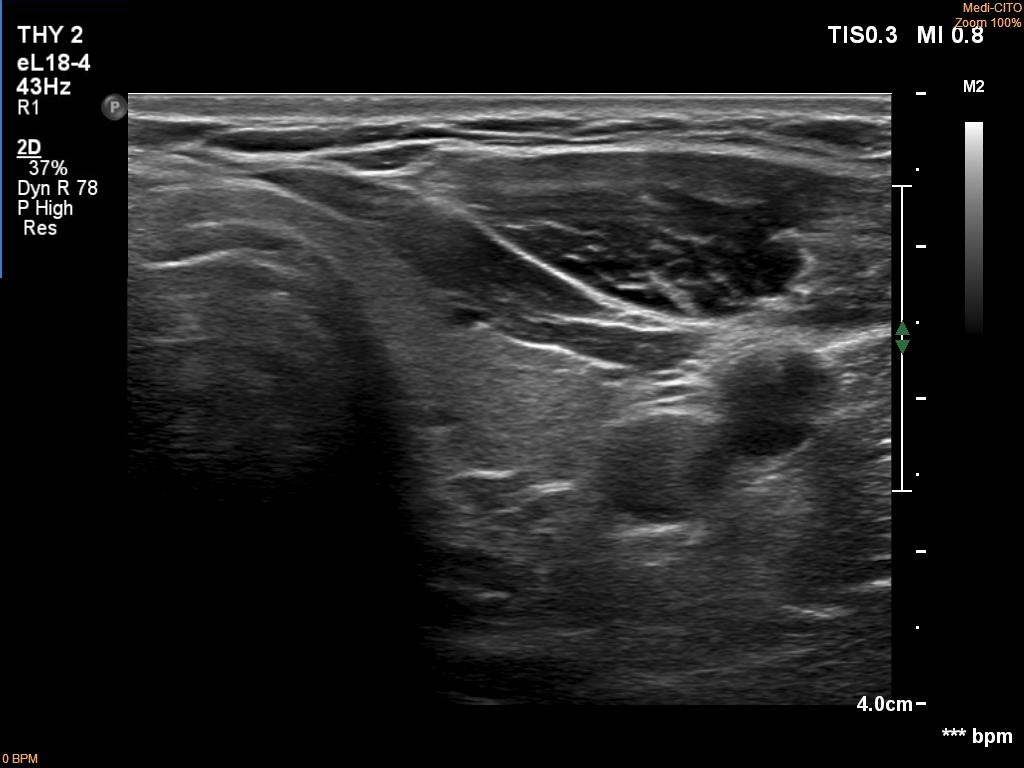

Ultrasonography. The thyroid was echonormal. There was a hypoechoic mass dorsal and under to the lower pole of the left thyroid lobe.